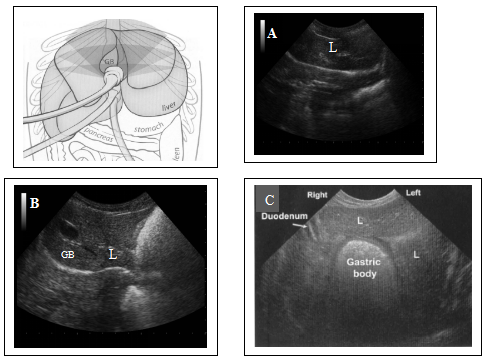

图4-1 正常肝脏的纵断面超声探查通路及声像图。探头从右(A)至左(C)进行扫查,可见胃肠与肝脏位置紧密,镰状韧带位于近场。不同动物的镰状韧带声像图变化较大,通常与动物的肥胖程度有关。肝脏血管(V)横断面表现为圆形的无回声结构。胆囊(GB)位于体中线的右侧。

图4-1 正常肝脏的横断面超声探查通路及声像图。犬仰卧位肋弓下扫查通路。A-C,横断面观,从颅腹侧(A)至尾背侧(C)进行扫查。胆囊位于体中线的右侧。